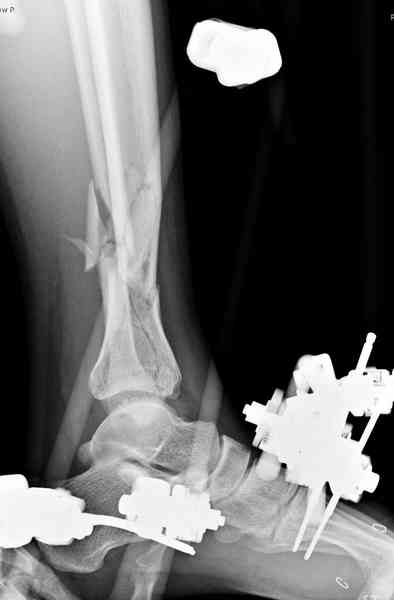

При высокоскоростных переломах редко можно встретить изолированную травму пилона, и в моей практике изолированные травмы большая редкость, поэтому, как дополнение к обсуждаемой теме, решил представить свежий, двухдневной давности случай.

Предыдущей сменой до 4:00 утра по поводу открытого перелома бедра, тибиал плато, пилон и надколенника сделана операция.

Пострадавшему 21 г., травма скоростная, после I&D с расширением раны, на бедре сделана операция ретроградным интрамедуллярным штифтом, остеосинтез с частичной резекцией надколенника и ушивание собственной связки.

На голень наружный фиксатор, рану на бедре ушили (рана была изнутри кнаружи всего 2 см). По протоколу травматических больных, до операции обследован ангиографически, (у больного дистально не смогли определить пульсацию) сосудистый хирург подтвердил проходимость на всем протяжении магистрального сосуда нижней конечности по снимкам ангиограмм.

В настоящее время больной в реанимации по поводу Черепно Мозговой Травмы и состояние улучшается. Запланировал ушивание раны в пятницу, если позволит состояние мягких тканей и при отсутстви отека возможно удастся просунуть перкутанномедиальную пластину.